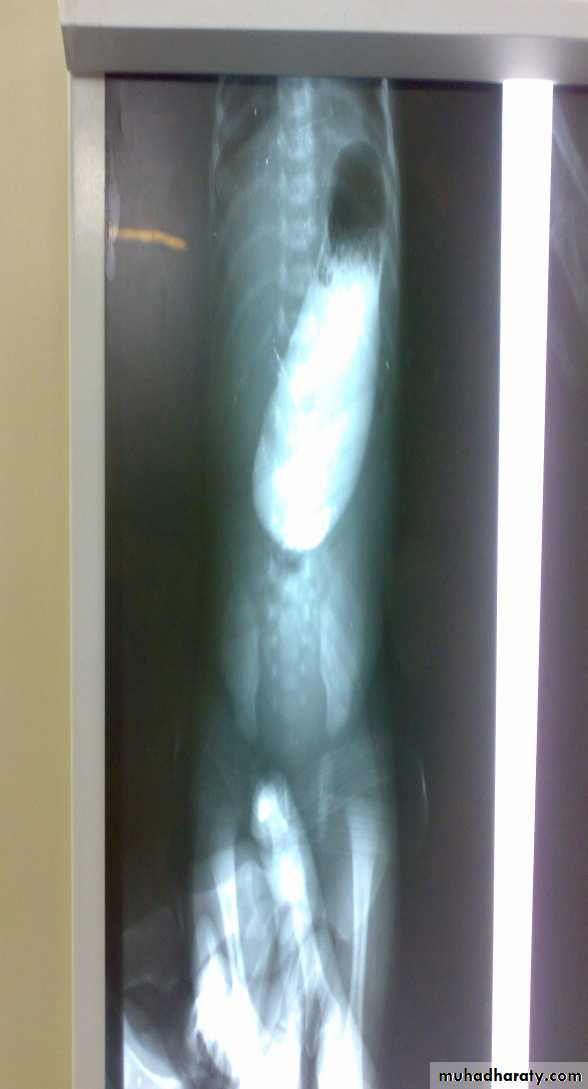

Diagnosis: pyloric stenosis(IHPS infantile hypertrophic pyloric stenosis—this name should be mentioned)

Presentation:

• Projectile vomiting (not present in first two weeks)• Olive mass in the abdomen

• Positive prestalsis(visible)

• FTT

Diagnosis:

• Clinically

• Ultrasound(width>14mm-length>16mm)

• Ba-meal dilated stomach – failure to pass to intestine – string sign

Treatment: in ER : resuscitation the pt(electrolyte+fluid)

surgery pyloromyotomy (rami stick surgery)Diagnosis: achalasia cardia